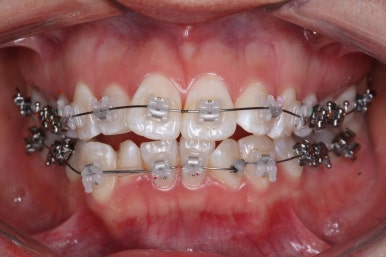

다시 이번 환자분으로 돌아가, 입 안모습을 보시겠습니다.

부산무턱교정 키다리아저씨치과에서 처음 내원하셨을 당시의 입 안의 모습입니다.

아래턱이 작아서 상대적으로 윗니들이 많이 돌출되었고, 뻐드러져 있습니다. 윗니들이 배열되어 있는 형태도 V자에 가깝게 입천장이 좁은 양상입니다.

장치를 부착하였습니다.

이번에 부착한 장치는 엠파워 클리어라고 하는 자가결찰 세라믹장치 입니다.

세라믹이기 때문에 덜 보이며 자가결찰 장치이기 때문에 초기에 가지런해지는 속도가 빠르고 통증이 덜한 장점이 있습니다.